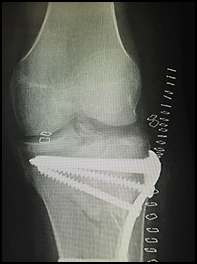

Radiografía de rodilla izquierda después de intervención quirúrgica (Imagen2)

Imagen 2. Fractura intervenida quirúrgicamente

Técnica Quirúrgica

Fracturas más complejas o con compromiso de la metáfisis como las tipo IV Y VI, se realiza anestesia general y se los coloca en decúbito dorsal en una camilla radio lúcida con la rodilla en 20° de flexión y un manguito neumático desinflado en la raíz del muslo. Realizamos campos quirúrgicos tomando desde la mitad del muslo hasta el pie y también la cresta iliaca. Primero se realiza una reducción percutánea más osteosíntesis transitoria con clavijas bajo control radioscópico. Una vez lograda una reducción aceptable, inflamos el manguito y comenzamos la fase artroscópica. Esta es de utilidad para valorar la reducción obtenida, corregirla si es necesario, como así también diagnosticar y tratar las lesiones asociadas. Si fuera necesario, en este momento se puede quebrar la camilla dejando la rodilla en 90°. La fijación la realizamos con la técnica MIPO, que consiste en la colocación de placas con tornillos por un abordaje mínimo (de aproximadamente 3 cm.) y la colocación de los tornillos, por vía percutánea.